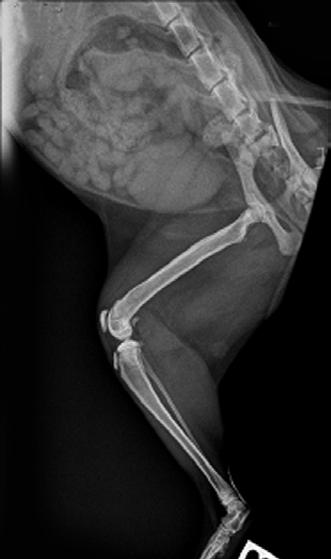

Tallulah presented as an 18-week-old Domestic Short Hair kitten with a persisting left forelimb lameness. On examination, she was uncomfortable on manipulation of the forelimb and painful on palpation over the left humerus. She was quiet and played for shorter time periods. She was in good body condition and eating well but had a temperature of 39.4° C. Radiographs suggested osteomyelitis of the left humerus, with extensive moth-eaten osteolysis of the diaphysis ( Figure 4).

She was given Amoxyclav (25mg/kg BID) and re-examined and radiographed 2 weeks later—by this time she was absolutely normal, with no pain or lameness and a normal temperature.

She is currently still on her antibiotics for 8 weeks before she is reviewed for repeat X-rays and spey!

3A 3B 4A 4B 3C

Figure 5. Lateral radiograph of the affected left leg (A) compared with the normal contralateral right leg (B) 2 weeks after stating amoxicillin clavulanate. Note the irregular areas of osteolysis of the left humerus are MUCH IMPROVED.

5A 6A 6B 5B

Figure 6. Lateral radiograph of the affected left leg (A) compared with the normal contralateral right leg (B) 8 weeks after stating amoxicillin clavulanate. Note the irregular areas of osteolysis of the left humerus are MUCH IMPROVED after extensive remodelling.